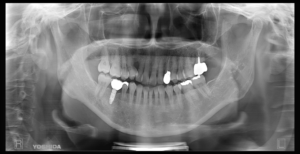

(治療後)

インプラントは単独での補綴物になるため、隣接歯への影響はなく、噛み合わせの再現もできる唯一の補綴物です。

▼第二治療終了後

経過も良好で、問題なく過ごしています。